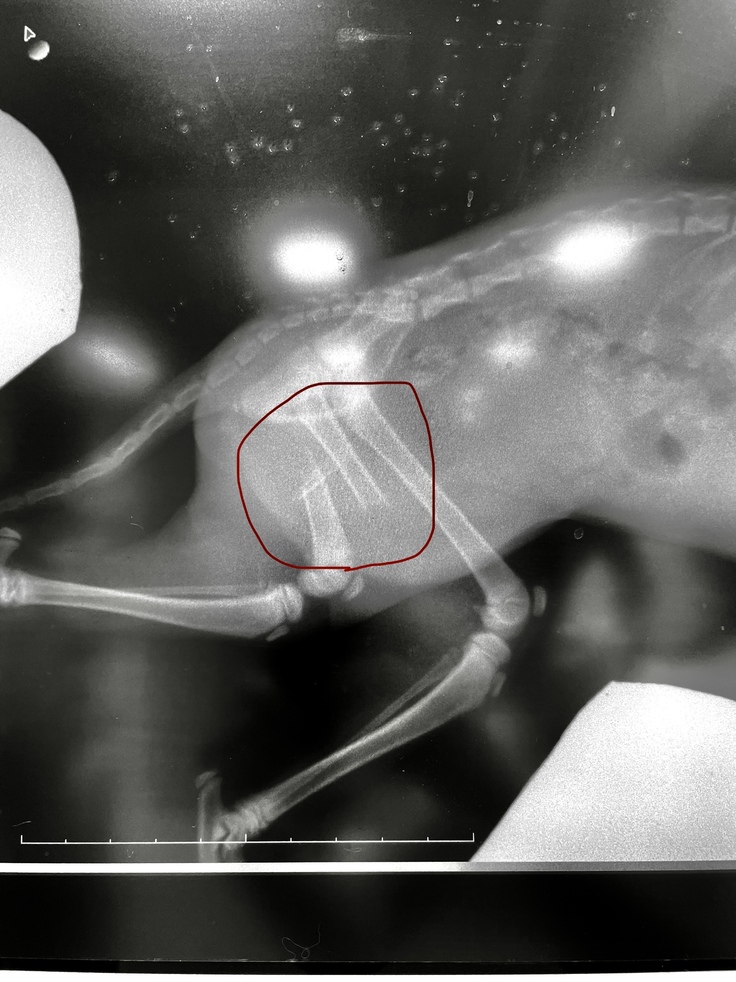

⑧受診(10月10日)

レントゲンを撮り怪我の経過を見て頂きました。最初は骨が散らばっていたので、まだ骨と骨との間に隙間はありますが経過は良好とのことでした!ワイヤーは入れたままで、今後も生活を送ります。

ピンを抜いたところは未だに噛んだり舐めたりしていて毛が薄いままです。皮膚の盛り上がりはかなり目立たなくなりました。

また前回の受診の時に心配していた毛が抜けたり薄くなった箇所は毛が生えてきました。

トイレが間に合わず排泄物を垂らしながらトイレへ行ったり、人の膝の上で排泄してしまう事を相談しました。まだ5ヶ月〜5ヶ月半ですので排泄機能については、しばらく様子を見ることになりました。

体重が増えて1.7kgになっていました!好き好みが出てきて、ご飯やおやつを選んで食べるようになってきてきます。

怪我の治療もひと段落したのでワクチン接種1回目も行いました。次回の受診は11月10日になります。そのときにワクチン接種2回目、マイクロチップ、避妊手術を行うため入院予定です。